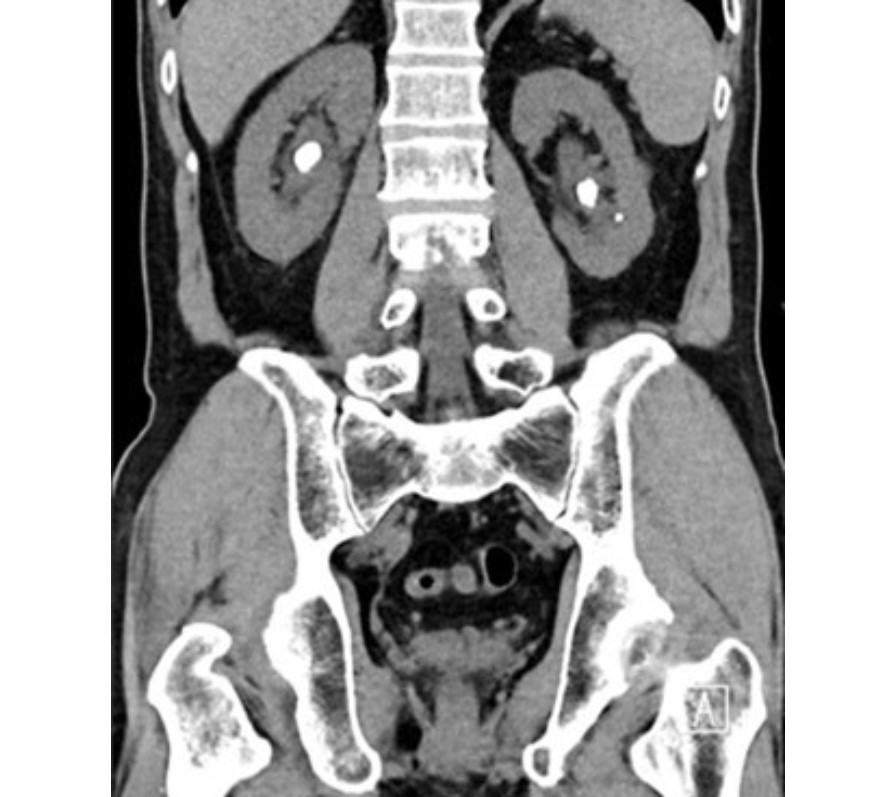

Renal Stones Clinical Features Management TeachMeSurgery Ct Scan Kidney Stone Protocol Kidney stone disease (nephrolithiasis) is a common problem in primary care practice. Is a ct scan necessary to diagnose kidney stones? Learn why your provider might order a scan. Scan from top of kidneys to bottom of symphysis pubis. Patients may present with the. R/o kidney or ureteral stones. Not all cases require imaging tests. Learn about the procedure, reasons,. Ct Scan Kidney Stone Protocol.

An overview of kidney stone imaging techniques Semantic Scholar Ct Scan Kidney Stone Protocol Scan from top of kidneys to bottom of symphysis pubis. Kidney stone disease (nephrolithiasis) is a common problem in primary care practice. If allergic to contrast or poor. R/o kidney or ureteral stones. Not all cases require imaging tests. Learn why your provider might order a scan. Learn about the procedure, reasons, risks, and preparation for a ct scan of. Ct Scan Kidney Stone Protocol.